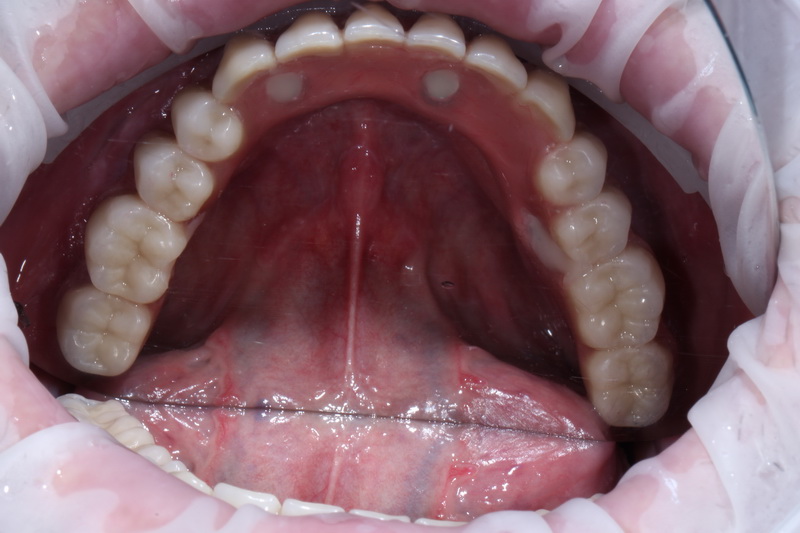

Діагноз з яким пацієнт звернувся в QRD Dental  повна адентія нижньої щелепи, лікарями було проведено детальне планування операції, розрахунок позицій імплантів,  фото протокол.

В день операції було проведено лікування, це – встановлення 4-х імплантів на нижній щелепі у попередньо сплановані позиції, з подальшим негайним навантаженням тимчасовим незнімним протезом.